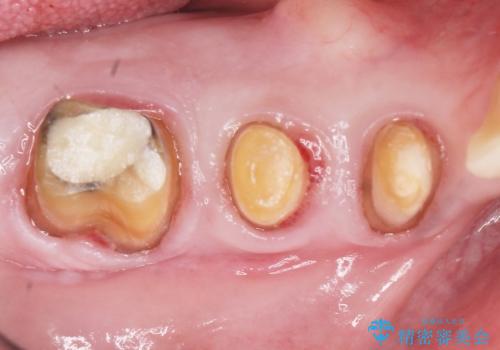

骨吸収の進行している右下臼歯部に、再生療法(骨を増やす手術))を行いました。

再生療法から1年後、リエントリー手術により骨の再生を確認し、骨外科処置(骨を平らにして歯周ポケットの根本的な改善を図る処置)を行いました。

- ¥670,000 (再生療法、骨外科処置、仮歯×3本、土台×1本、被せ物×3本)費用は治療当時の料金となります